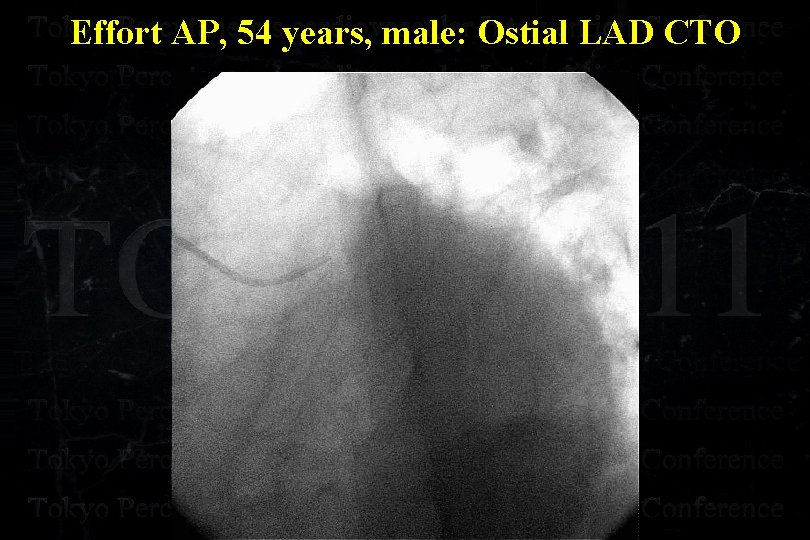

Effort AP, 54 years, male: Ostial LAD CTO

Effort AP, 54 years, male: Ostial LAD CTO

Effort AP, 54 years, male: Ostial LAD CTO

Effort AP, 54 years, male: Ostial LAD CTO

Effort AP, 54 years, male: Ostial LAD CTO